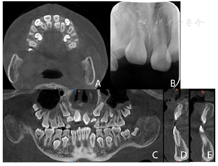

CBCT示:上颌恒牙胚萌出间隙不足,根据Moyers混合牙列分析法,牙弓现有长度为177.4 mm,牙弓应用长度为181.6 mm,拥挤度为4.2 mm。42缺失;11、21、22发育至Nolla9期;55、16、65、46冠部低密度影及牙本质中层,根管内未见高密度充填影,根尖周未见明显异常。53、63牙根吸收不足1/3,13、23发育至Nolla8期。

2020年10月11日门诊局麻下摘除下颌双侧前磨牙区多生牙及其牙囊3颗。

2020年12月21日口腔颌面部CBCT精确定位、笑气镇静+4%肾上腺素-盐酸阿替卡因注射液局部浸润麻醉下先行拔出恒中切牙腭侧多生牙,同期切除部分牙龈暴露双侧上中切牙牙冠最宽径。4个月后11仍未有萌出迹象,21萌出,与31反

垫舌簧活动矫治器利用后牙区乳牙及已萌恒牙作为支抗对11进行橡皮链牵引,并在12、21及22舌侧增加舌簧。活动矫治器在上颌腭部增加螺旋扩弓器,对上颌骨进行慢速扩弓纠正其横向发育不良。因无确切证据表明上颌存在失状方向上发育不足,故暂不考虑佩戴上颌前方牵引器。11橡皮链牵引持续6个月,扩弓持续11个月,扩弓结束后保持3个月。

患者初诊时根据恒牙发育Nolla分期诊断该患者11、21、22迟萌,其可能原因与腭侧多生牙、11牙根弯曲及可能患有颅骨锁骨发育不全综合征相关。

本例患者后续矫治期间陆续查及多生牙6颗,分别位于上颌前牙区及下颌双侧磨牙区,下颌磨牙区多生牙位于颌骨深处且无萌出通道,对邻近牙造成牙根吸收的风险,上颌区多生牙位于恒前牙萌出通道上,因此对于此患者口内多生牙均不予保留,采取外科手术方法拔除。